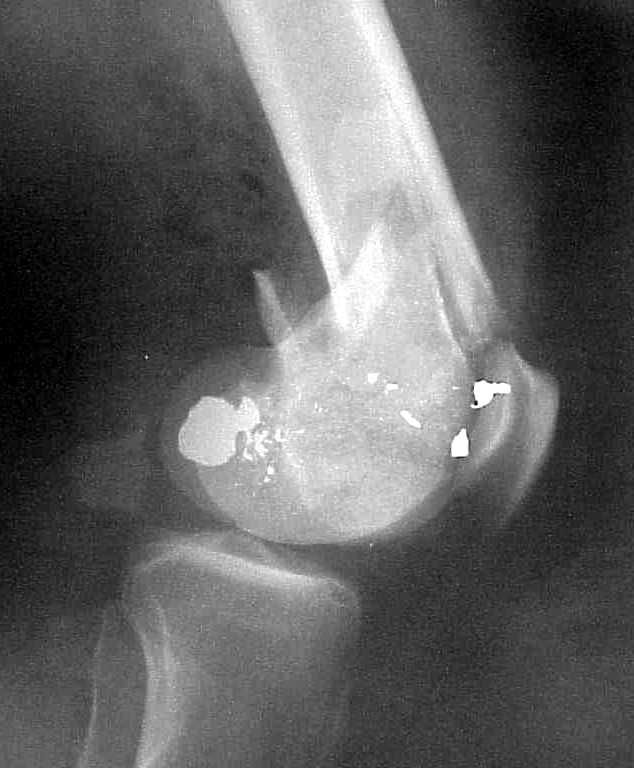

A CT and knee xrays would help identify lateral condyle comminution and/or a "hoffa fragment" of the posterior condyle. I am concerned that the lateral cortex is not sufficient to give purchase for a retrograde IMN. blocking screws could improve this as a possibility. A long blade or LISS if avaible would be my secondary choices. Good luck. Any chance you can get these cases transferred earlier when it

Use 6.5 mm cannulated screws if you have and

place one anterior to where IMN will go if anterior cortex if insufficient and AP screws on either side of the IMN out of the trochlea to provide some additional varus/valgus stability. I worry about the leg going into valgus w/the lack of lateral cortex.

See attached case that was done several years ago before LISS. He had comminuted trochlea and anterior blocking screws were used to prevent anterior IMN cut-out.